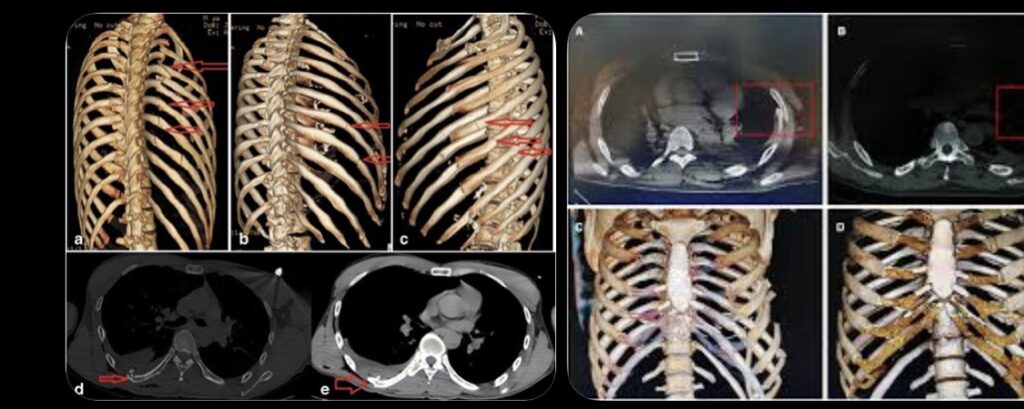

En el mensaje, explicó que sufrió “11 costillas rotas o 11 cosas en mis costillas”, comparándose con el personaje de Forrest Gump por la magnitud del percance.